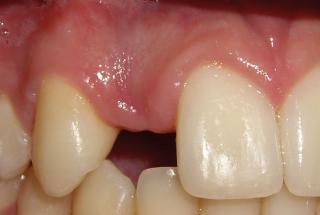

Clinical cases

MPI closely monitors clinical cases in the market to ensure their correct functioning and successful outcome.